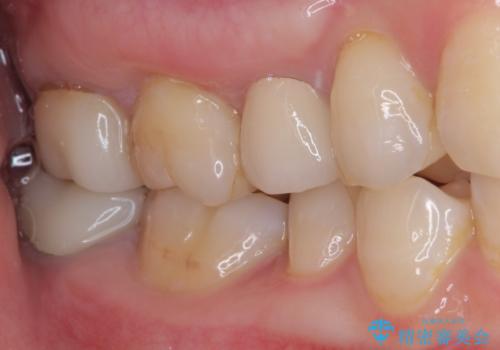

- 見た目の不揃いなセラミックと、痛みを感じる歯を気にして来院された患者様です。

右上の歯は噛んだときに何カ所か痛みを感じるとのことで、診査したところ第二小臼歯が患歯と疑われました。

患者様は他の歯にも痛みを感じるとおっしゃっていましたが、そのような所見が認められなかったため、まずは第二小臼歯を処置し、その痛みが引いた後に再診査することとしました。

痛みが引いた後、不揃いな見た目で気になっていた左下の奥歯とともにオールセラミッククラウンにて補綴治療を行うこととしました。

右上の歯は、第二小臼歯の初回処置後に痛みを感じなくなったため、他の歯については問題なしと診断しました。

将来ホワイトニングをされるとのことで、前歯よりもやや白い色合いのオールセラミッククラウンを選択されました。